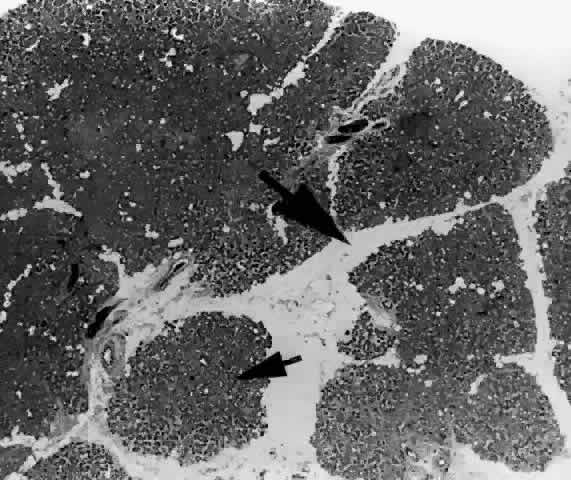

Each lobe of the lacrimal gland is separated into numerous lobules by interlobular fibrovascular connective tissue (Fig. 11). Each lobule, as seen by light microscopy, is composed of two units (Fig. 12): (1) the acinar unit (or secretory unit); and (2) the ductal system. The acinar units are further separated by intralobular fibrovascular connective tissue.

Fig. 11. Lacrimal gland architecture. Each lobe of the lacrimal gland is separated into numerous lobules by interlobular fibrovascular connective tissue. (H & E, original magnification × 5; Courtesy of Ralph Eagle, MD, Philadelphia, PA)